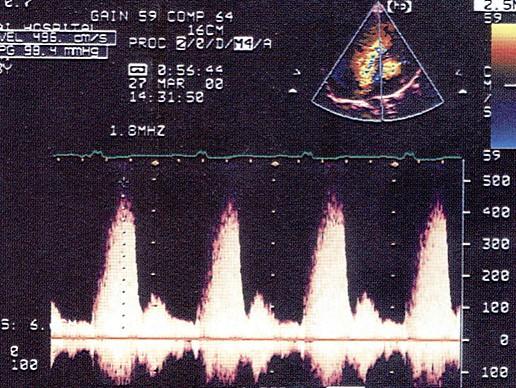

该病例最可能的诊断?(?)A.主动脉窦瘤B.室间隔缺损C.右室流出道狭窄D.室间隔膜部瘤并破裂E.以上都不是

问题 该病例最可能的诊断?(?)

选项 A.主动脉窦瘤 B.室间隔缺损 C.右室流出道狭窄 D.室间隔膜部瘤并破裂 E.以上都不是

答案 D